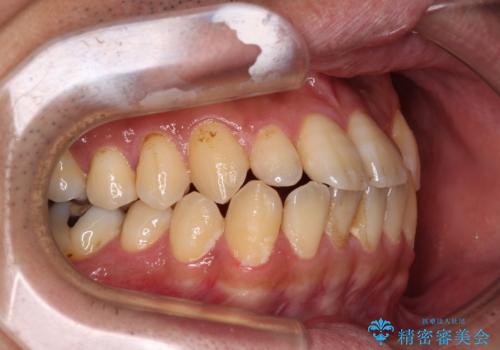

内側に引っ込んだ歯を治したい インビザラインの矯正治療

- 前歯のデコボコとクロスバイトを治したいとのことで来院された患者様です。

上下顎ともに歯列全体の側方拡大とIPR(歯と歯の間を削る)によってデコボコとクロスバイトが解消するように設計し、インビザラインにより治療を行うこととしました。

反対咬合特有の治療途中の前歯の干渉が長く続き、治療中に食事をとりにくく、ご迷惑をおかけしました。

前歯の咬み合わせの調整などを行い、安定した咬み合わせに仕上げることができました。